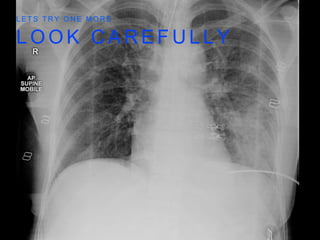

L E T S T R Y O N E M O R E

CLAVICLE #

ROTATION

OF RIBS

L O OK C A R E F U L L Y L E T S T R Y O N E M O R E

• 7.